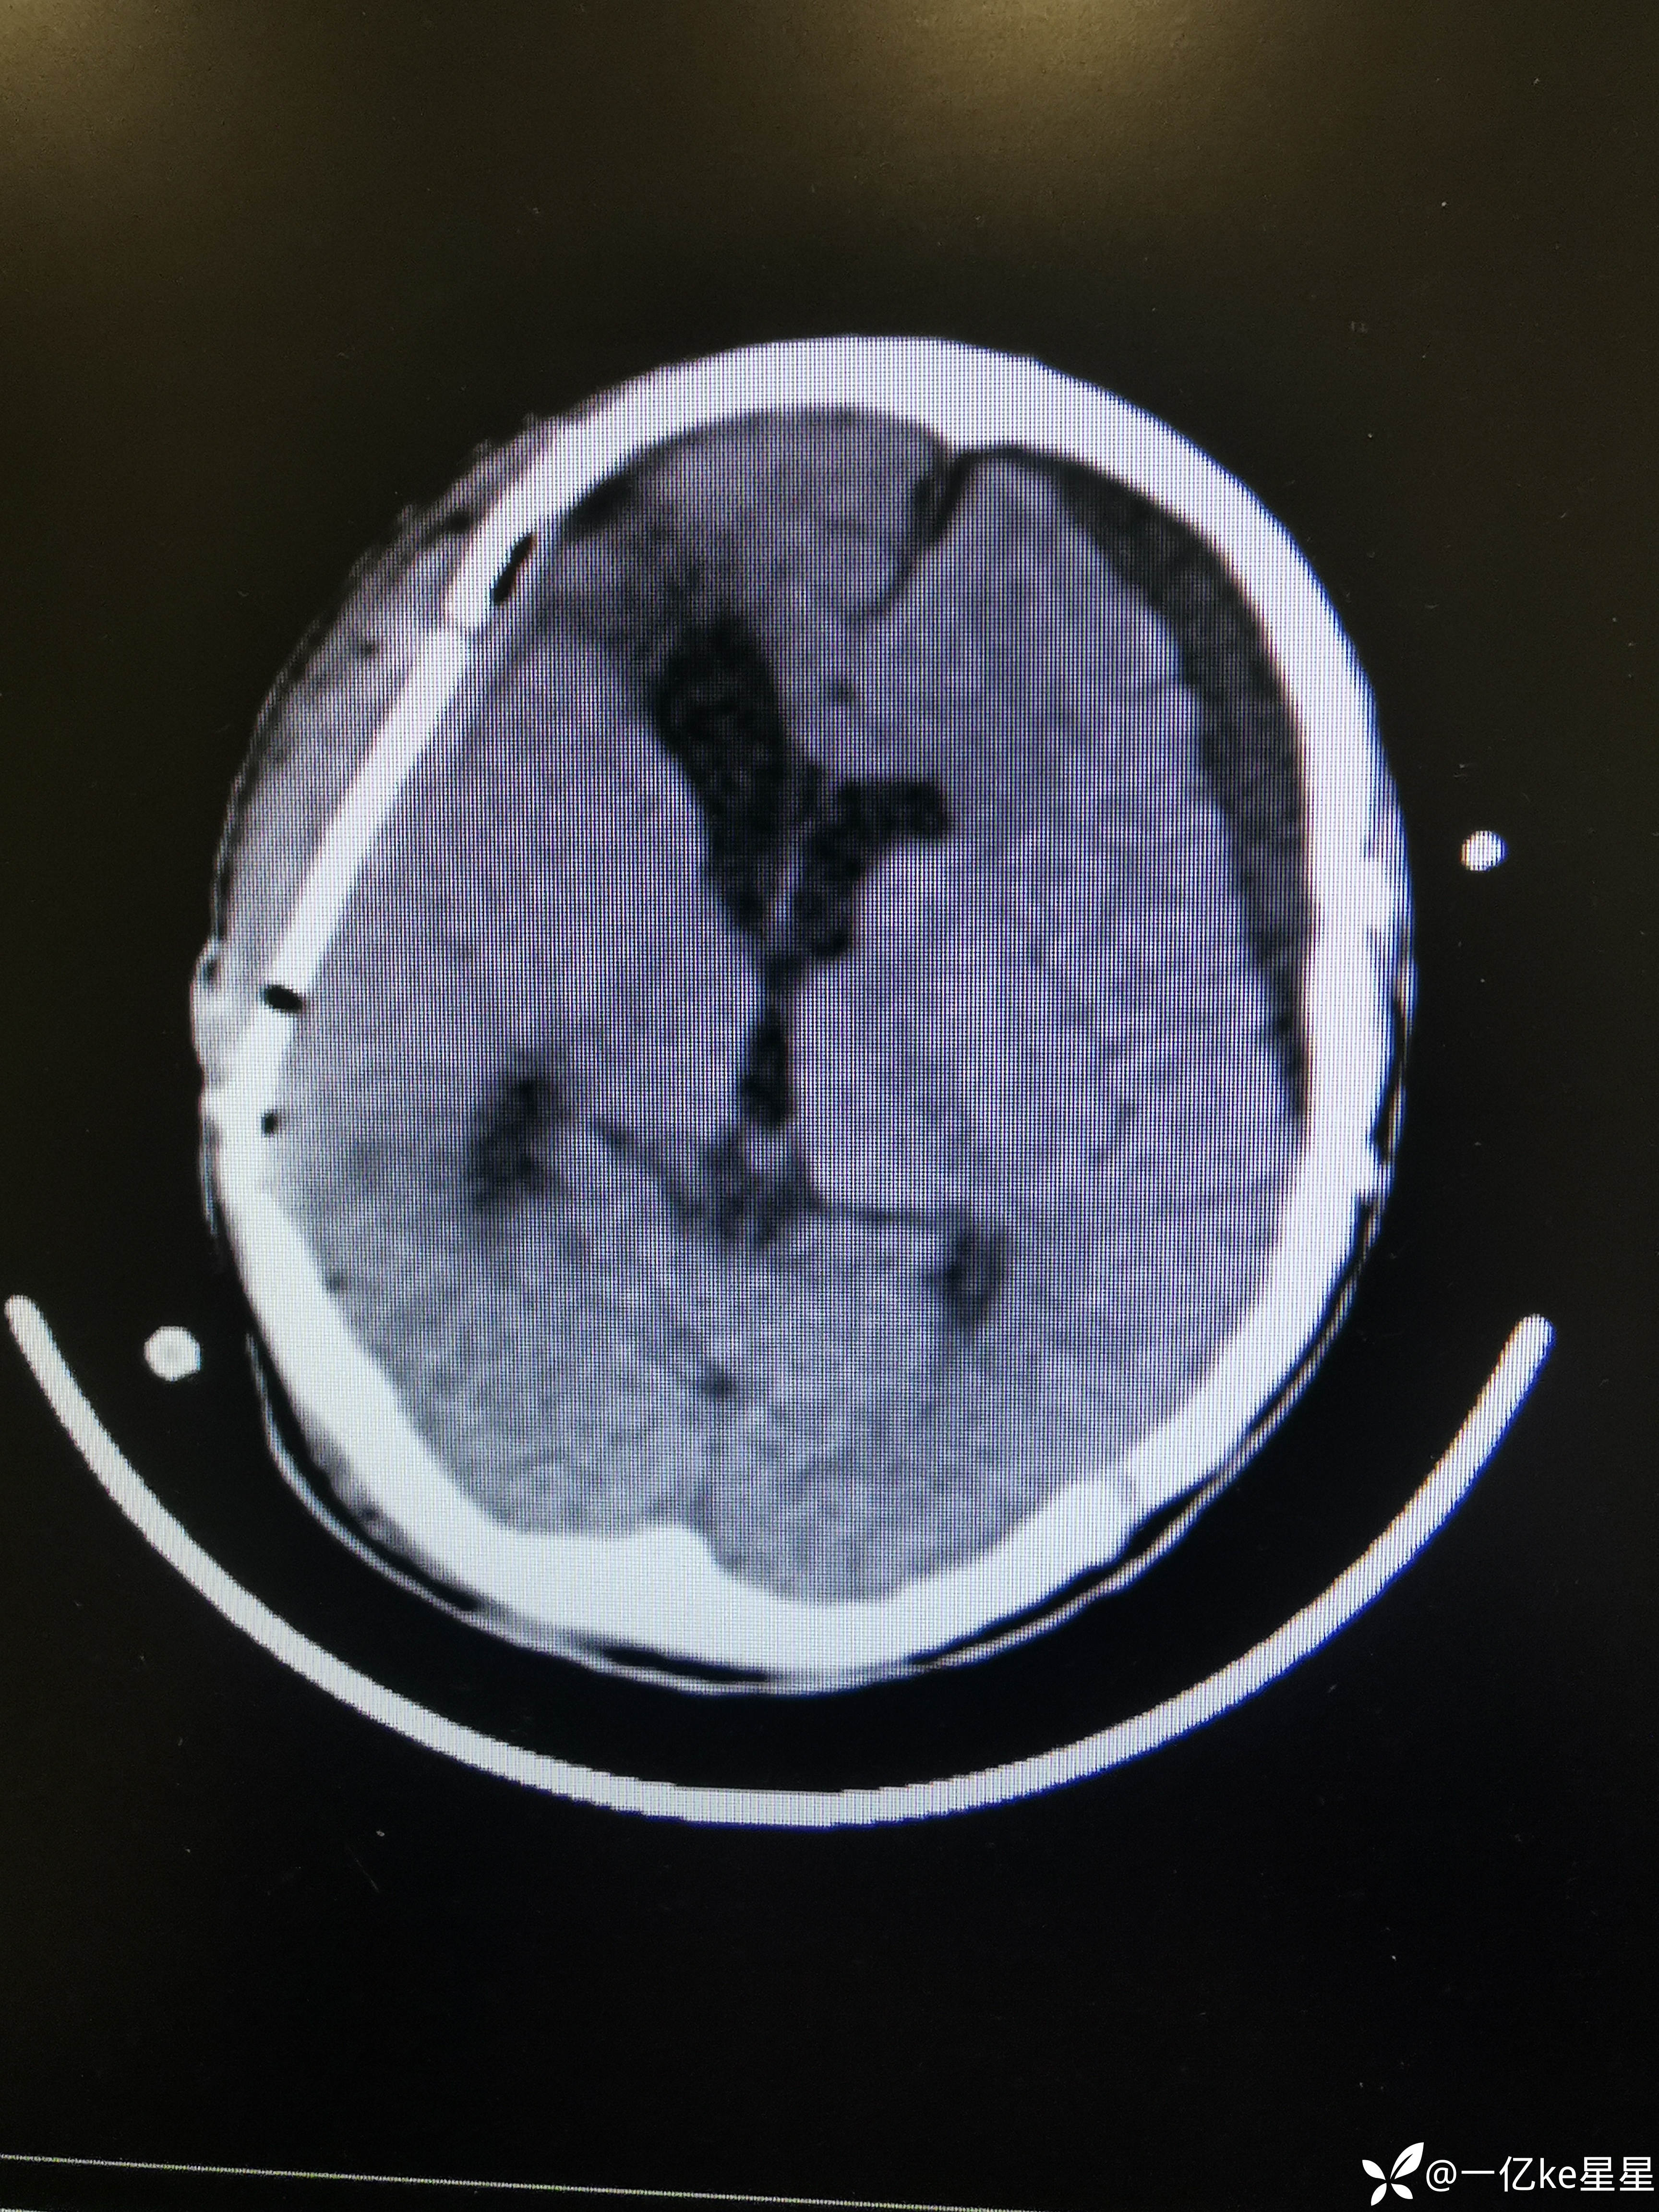

医者超哥等 2人推荐患者车祸伤致意识障碍50余天。当地查头颅CT:脑出血、急性硬膜下血肿,当地行颅内血肿清除术+去骨瓣减压术,患者意识昏迷,行气管切开,术后复查对侧再次出血,遂再次行颅内血肿清除术,术后对症治疗(具体不详),后患者意识恢复差,间断体温高、心率快,为求进一步治疗,就诊于我院,考虑患者左侧硬膜下积液增多(2023.11.7)

给予锥颅及腰穿后效果欠佳,于神外行颅骨修补术(2023.11.14)